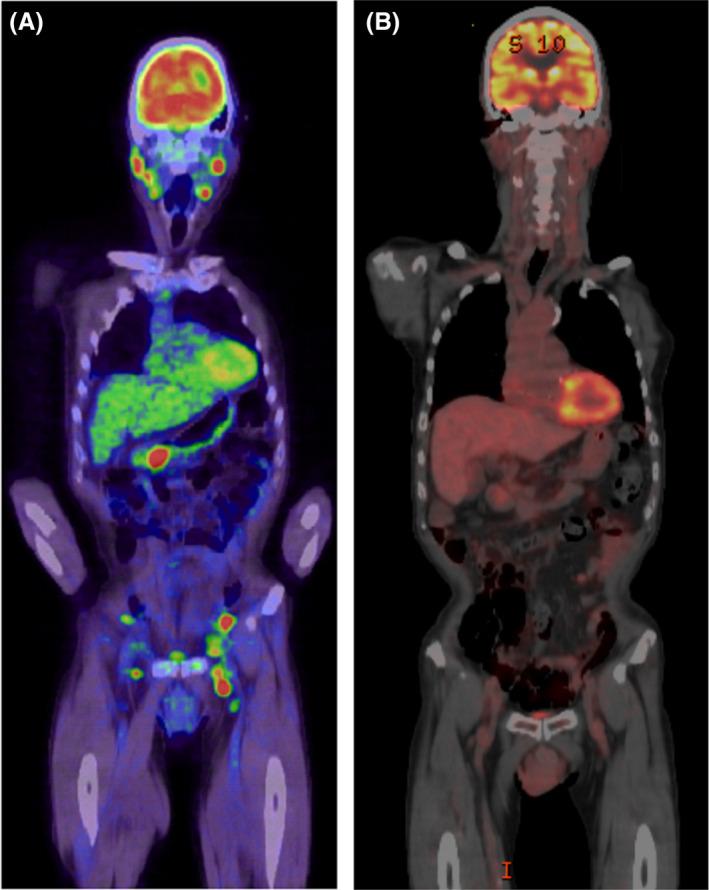

Tyrosine kinase inhibitor (TKI) can help to increase the survival time in chronic myeloid leukemia (CML) patients; however, the risk of secondary malignancies due to TKIs is a growing concern. Only few reports showed clinical course of patients who developed lymphoma during TKI therapies. Herein, we report a case of high-grade B-cell lymphoma diagnosed in the course of CML treatment with bosutinib. The 75-year-old male patient had been diagnosed with CML 25 years ago. After receiving TKIs (imatinib, nilotinib, and bosutinib), he achieved a major molecular response. Over 3 years after starting bosutinib, he was diagnosed with a high-grade B-cell lymphoma. A total of six courses of DA-EPOCH-R therapy brought complete remission of the lymphoma. Moreover, BCR-ABL1 transcript copies remained undetectable by RT-PCR, 8 months after stopping bosutinib. The risk of secondary malignancy due to TKI has been controversial. It is reported that TKI induces irreversible chromosomal abnormalities or chromosome aberrations and inhibits the proliferation or function of T cells, B cells, and NK cells. These mechanisms of TKI may contribute to the development of secondary malignancy. There remains no consensus on the management of secondary lymphoma during TKI therapies. At present, the only alternative is to observe patients receiving TKI treatment cautiously and to treat secondary lymphoma in the same manner as de novo lymphoma.

酪氨酸激酶抑制剂(TKI)有助于延长慢性髓性白血病(CML)患者的生存时间;然而,TKI导致继发性恶性肿瘤的风险日益受到关注。仅有少数报告显示了在TKI治疗期间发生淋巴瘤的患者的临床病程。在此,我们报告1例在使用博舒替尼治疗CML过程中诊断出的高级别B细胞淋巴瘤病例。该75岁男性患者于25年前被诊断为CML。在接受TKI(伊马替尼、尼洛替尼和博舒替尼)治疗后,他达到了主要分子反应。开始使用博舒替尼3年多后,他被诊断出患有高级别B细胞淋巴瘤。总共六个疗程的DA-EPOCH-R治疗使淋巴瘤完全缓解。此外,在停用博舒替尼8个月后,通过RT-PCR检测不到BCR-ABL1转录本拷贝。TKI导致继发性恶性肿瘤的风险一直存在争议。据报道,TKI会诱导不可逆的染色体异常或染色体畸变,并抑制T细胞、B细胞和NK细胞的增殖或功能。TKI的这些机制可能促使继发性恶性肿瘤的发生。对于TKI治疗期间继发性淋巴瘤的管理尚无共识。目前,唯一的选择是谨慎观察接受TKI治疗的患者,并以治疗原发性淋巴瘤的相同方式治疗继发性淋巴瘤。